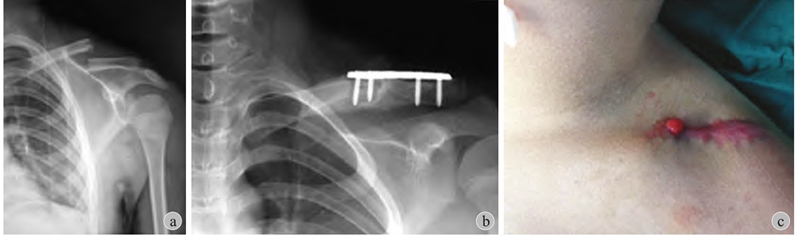

图4 患儿 男 10岁

a:左锁骨骨折应考虑保守治疗;b:外院行切开复位+接骨板固定;c:术后发生感染及骨髓炎